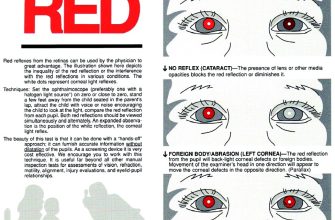

Leukocoria, also known as the white pupil, is an eye